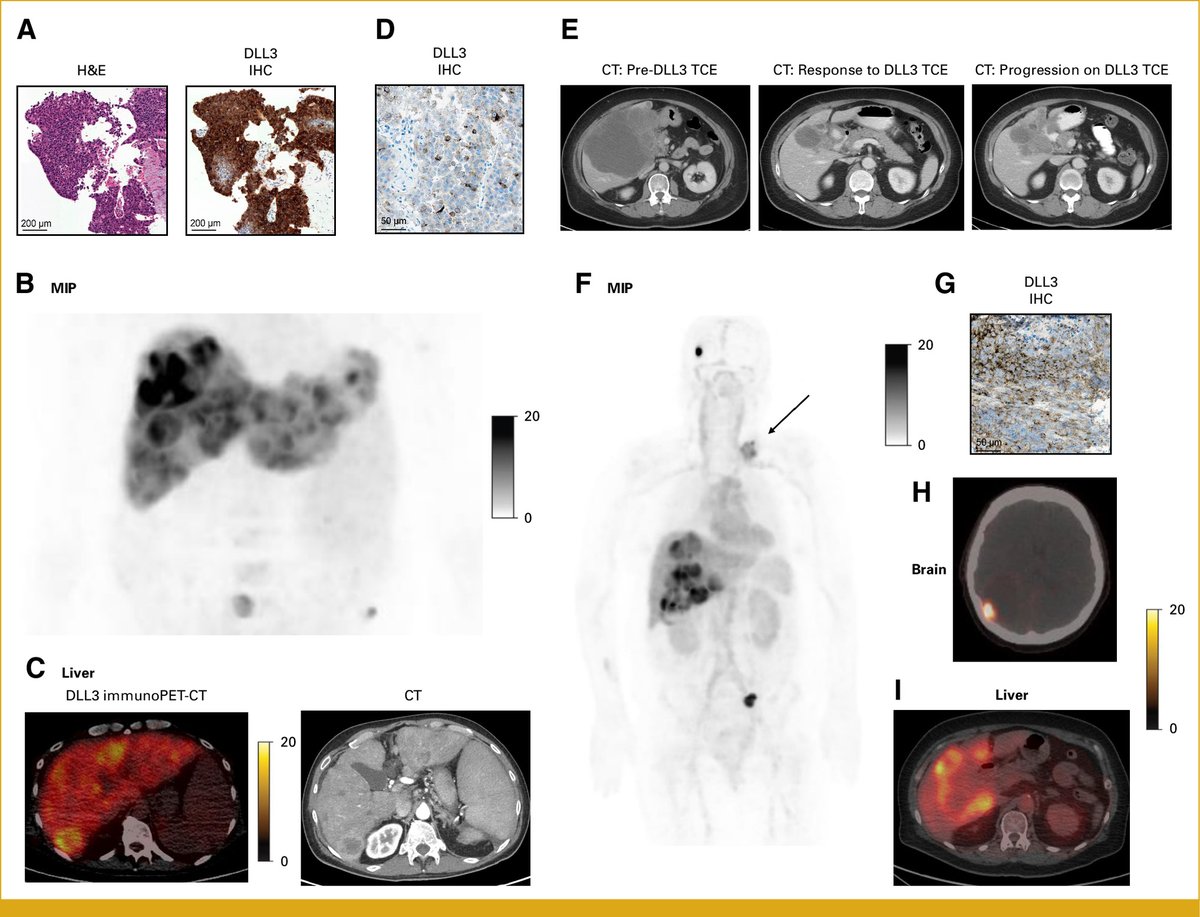

@JCOPO_ASCO (4/X) We next performed 89Zr-SC16.56 functional DLL3 immunoPET-CT imaging in patients with DLL3 IHC-positive disease, describing high level functional DLL3 tumor avidity both in patients with GEP NECs (left) and G3 well differentiated pancreatic NETs (right).

@JCOPO_ASCO (3/X) Among well differentiated GEP NETs, we describe DLL3 expression in ~40% of high grade (G3) tumors, most commonly G3 pancreatic NETs, and describe association of DLL3 expression and poor outcomes with standard therapies in pancreatic NETs.

@JCOPO_ASCO (2/X) First, we describe DLL3 IHC expression in ~70% of poorly differentiated GEP NECs across primary sites of disease, with enrichment for small cell histology, supporting multiple ongoing therapeutic efforts in this space.

DLL3 in GEP-NENs: new therapeutic window 🔥 High DLL3 expression: 71% GEP-NECs, 40% G3 NETs, esp. PanNET G3 (43%) ⚠️ DLL3+ G3 PanNETs → worse survival (HR 3.27) 🧪 DLL3-immunoPET detected avid lesions in 5/6 patients 💡DLL3: promising target for NEC & high-grade PanNETs 🔗